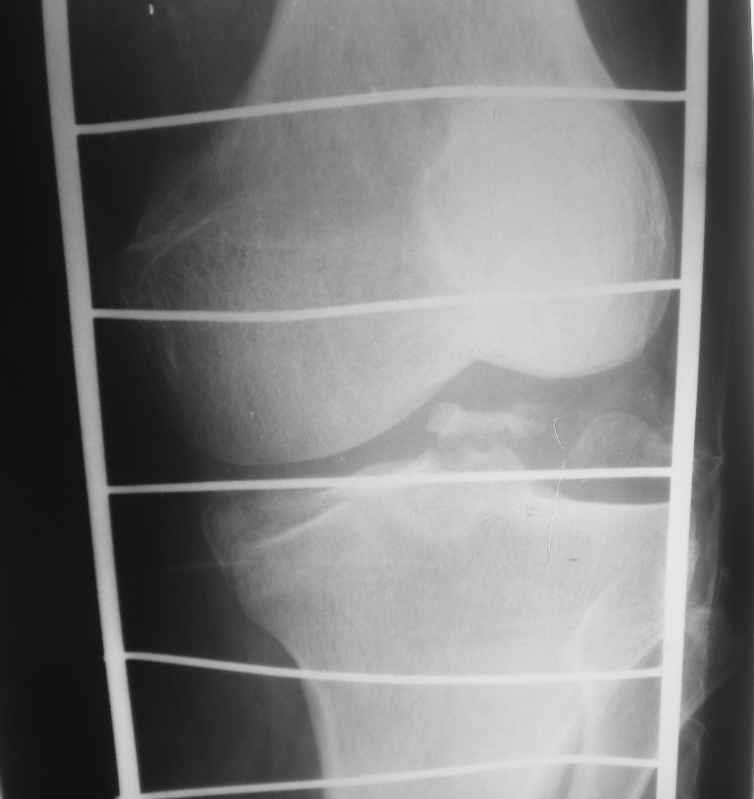

Высылаю рентгенограммы

1 совсем не уверен, что авульсию латеральной коллатеральной связкис маленьким фрагментом головки малоберцовой Вам удастся зафиксировать винтом или проволкой. Будьте готовы к другим методам фиксации или реконструкции связочного аппарата

2 если медиальный мыщелок - чистая импакция, без среза ( похоже на то по снимкам) - пластина, в общем-то, не нужна, достаточно "поднять" суставную поверхность, трансплантат ( совсем не обязательно аутотрансплантат - вполне подойдет автоклавированная чья-то головка бедра) и поддержать суставную поверхность парой крупных шурупов.

3 если есть возможность - было бы очень здорово перед операцией сделать КТ - можете найти много чего неожиданного